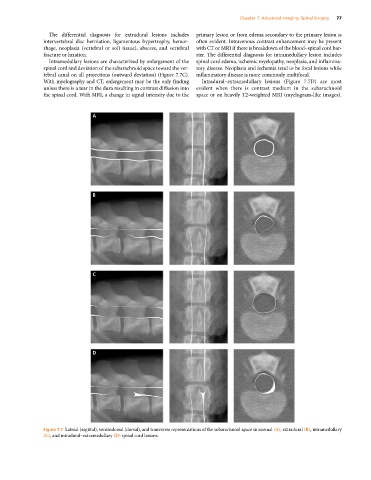

Intramedullary lesions are characterized by enlargement of the spinal cord edema, ischemic myelopathy, neoplasia, and inflamma

spinal cord and deviation of the subarachnoid space toward the ver tory disease. Neoplasia and ischemia tend to be focal lesions while

tebral canal on all projections (outward deviation) (Figure 7.7C). inflammatory disease is more commonly multifocal.

With myelography and CT, enlargement may be the only finding Intradural–extramedullary lesions (Figure 7.7D) are most

unless there is a tear in the dura resulting in contrast diffusion into evident when there is contrast medium in the subarachnoid

the spinal cord. With MRI, a change in signal intensity due to the space or on heavily T2‐weighted MRI (myelogram‐like images).

Figure 7.7 Lateral (sagittal), ventrodorsal (dorsal), and transverse representations of the subarachnoid space in normal (A), extradural (B), intramedullary

(C), and intradural–extramedullary (D) spinal cord lesions.